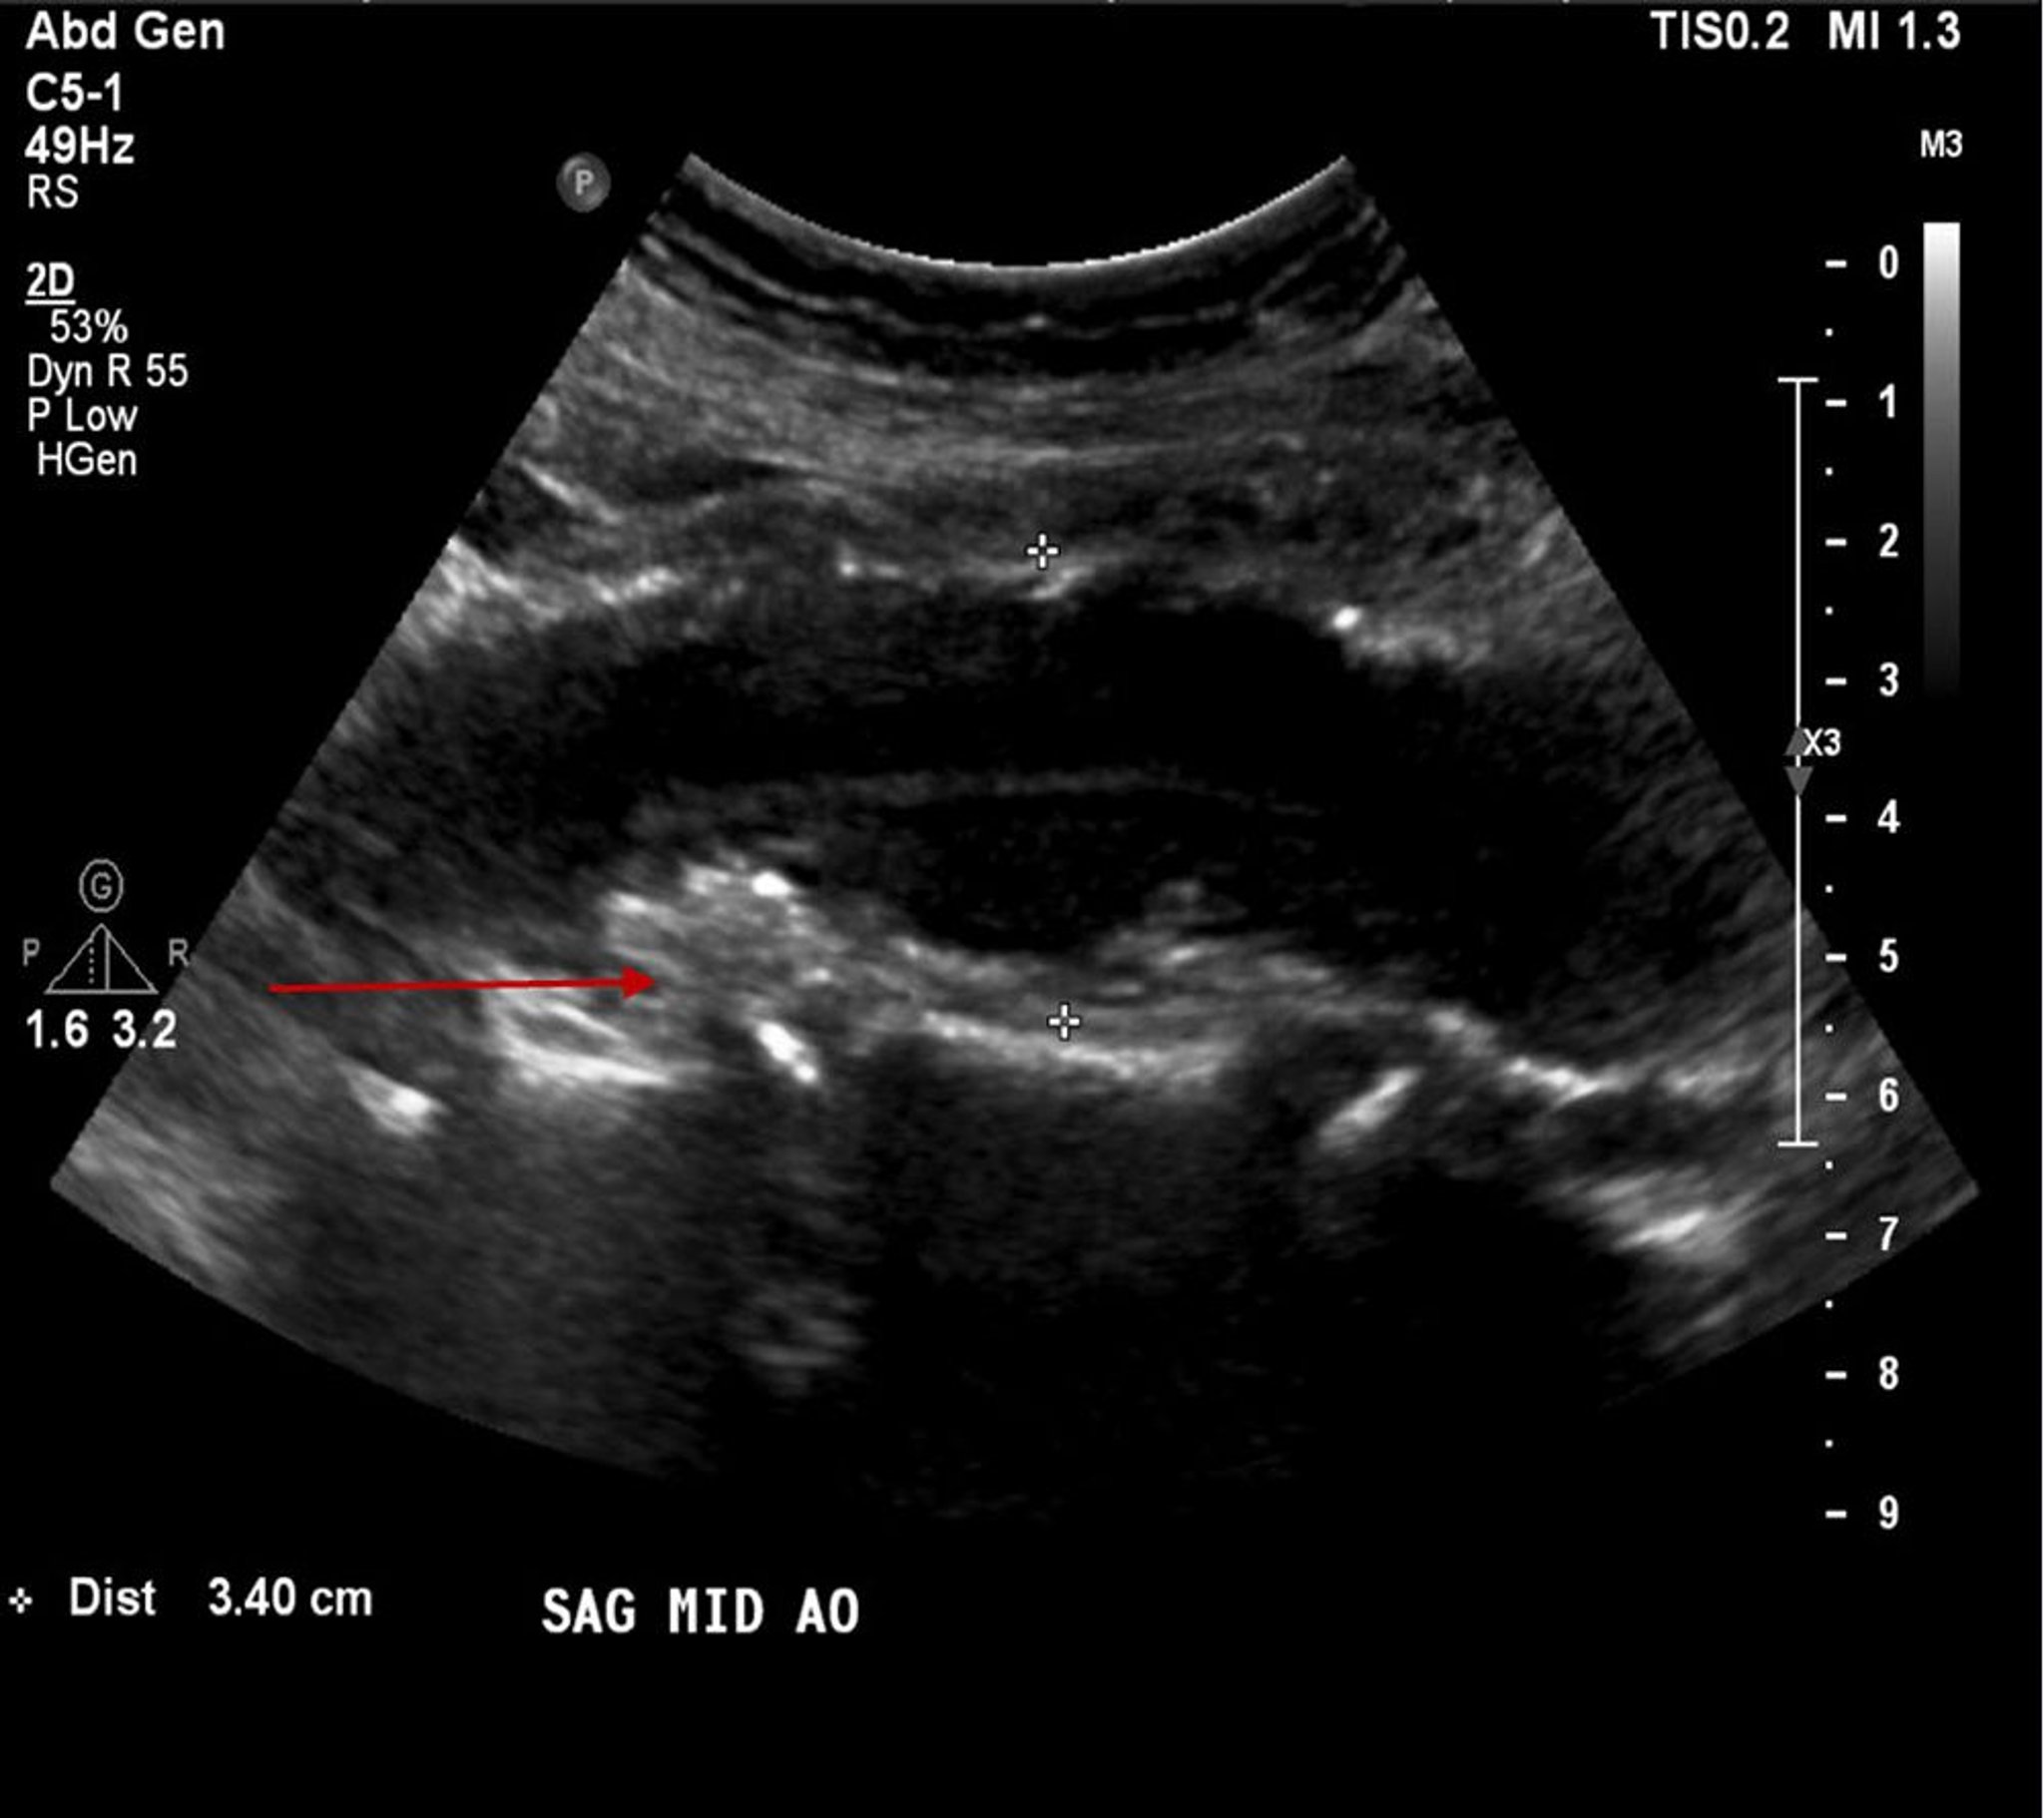

Phình động mạch chủ bụng (siêu âm)

Bệnh nhân này có một túi phình động mạch chủ bụng có kích thước 3,4 cm (giữa hai chữ thập màu trắng) cũng như mảng xơ vữa động mạch hoặc cục nghẽn trên thành (mũi tên đỏ).